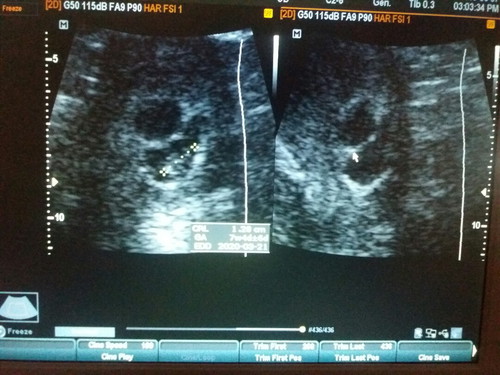

2 gestational sacs

Hi mga mommies, Im 8 weeks preggy, 26 yrs old. Ask lang po ako if possible po na twins yung magiging babies ko? Dalawang gestational sac kasi ang nakita ng OB ko nung nag pa ultrasound ako last week, pero isang baby lang po ang nakita and malakas po heartbeat, yung isang sac naman po is wala pang baby na makita. Ano po sa tingin nyo? Hehe. Excited mom here. ?